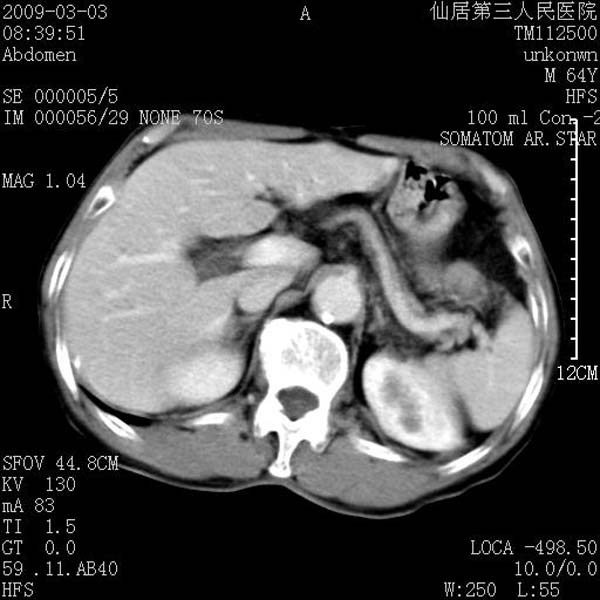

标题: CT18469:男性,64y,体检B超示肝脏低回声肿块,有胃溃疡手术 [打印本页]

患者,男性,64y,体检b超示肝脏低回声肿块,有胃溃疡手术史。

考虑----胃肠道间质瘤可能性大

从平扫及增强的特点来看,支持肝脏腺瘤并出血。

考虑胃间质瘤可能性大。

胃肠道间质瘤!

ct值呢?感觉没强化,象囊性。

考虑肝静脉韧带裂区良性占位性病变(囊肿?)。

考虑肝囊肿并出血可能性大.

考虑高密度囊肿可能性大